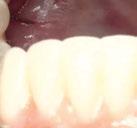

aproximadamente una hora y media. Usamos resina Bego VarseoSmile TriniQ® para puentes definitivos. Aunque en este caso la vamos a usar para confeccionar unas prótesis fijas atornilladas provisionales de larga duración, dado al aumento de dimensión vertical que vamos a realizar a la paciente, de esta forma obtendremos una neuroprogramación de la ATM reinstaurando una Dimensión Vertical apropiada y mejorando la estética facial de la paciente. Excluimos de la carga aquellos implantes que no obtuvieron una estabilidad primaria superior a 35 N/ cm2. El material permite la realización de una carga inmediata en material definitivo en puentes (Figuras 31 a 38).

Figura 36. Carga inmediata provisional recién atornillada.

Figura 37. Resultado final visión frontal. Figura 38. Resultado final visión lateral.